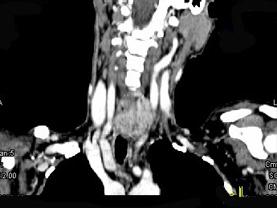

问题 女,50岁,左下颈部扪及一质硬、表面高低不平的包块,约半年,肿块逐渐增大,现感吞咽困难。如图所示CT诊断为 ( )

选项 A、甲状腺原发淋巴瘤 B、颈部神经鞘瘤 C、食管癌 D、喉癌 E、甲状腺癌

答案 E